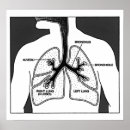

COPD Lung diseases diagram Poster

PriceCA$32.35